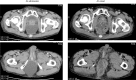

Presentation of case: A 75-year-old man undergoing treatment for alcoholic cirrhosis underwent laparoscopic abdominoperineal resection of the rectum (APR) for lower rectal cancer after preoperative chemoradiotherapy. Lung metastases were diagnosed 2 months postoperatively. Ten days after chemotherapy initiation, the patient was hospitalized on an emergency basis due to hepatic encephalopathy. Ten days thereafter, we observed perineal skin protrusion. Moreover, the skin disintegrated spontaneously, resulting in ascetic fluid outflow. Pain and fever developed, with inflammatory reactions. Contrast-enhanced computed tomography showed strangulated small bowel obstruction due to perineal hernia. We performed an emergency surgery, during which we found small intestine wall incarcerated in the pelvic dead space, with thickening and edema; no necrosis or perforation was observed. We performed internal fixation by introducing an ileus tube into the ileocecum and fixing its balloon at the cecal terminus.